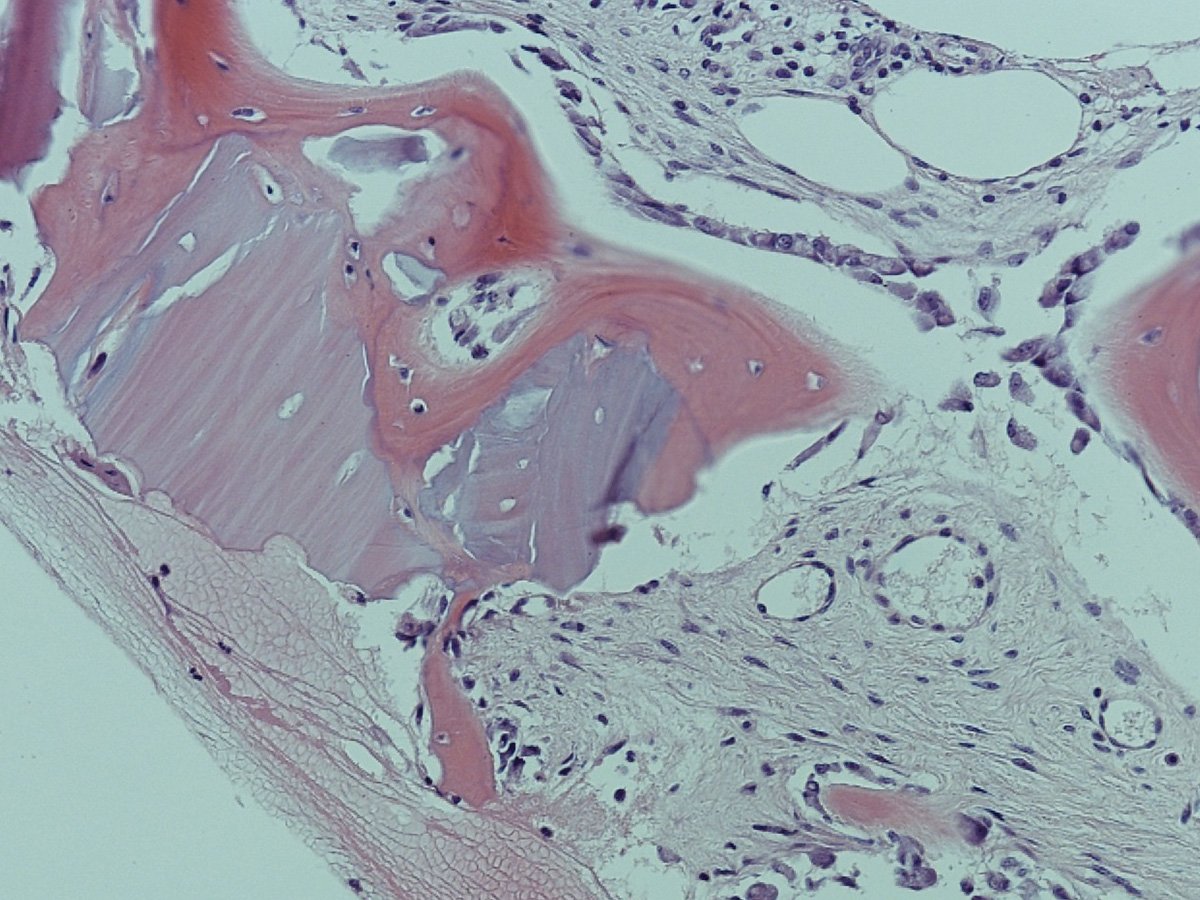

Abbildung 10

Abbildung 11

Histologie bei stärkerer Vergrößerung: In den Resorptionslakunen sind Osteozyten erkennbar.